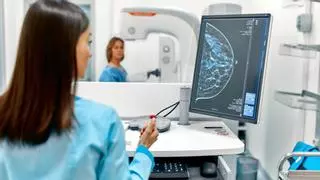

La Conselleria de Sanidad invertirá tres millones en 10 mamógrafos nuevos para agilizar las pruebas

La Generalitat introducirá en el diagnóstico la inteligencia artificial en cuatro hospitales, entre ellos el de Alicante

Un mamógrafo del centro de salud de Altabix, en Elche / Antonio Amorós

Asimismo, ha explicado las modificaciones que está llevando a cabo su departamento en el programa de prevención y ha anunciado una inversión de tres millones de euros en la compra de 10 nuevos mamógrafos para sustituir a los obsoletos y prevé introducir la inteligencia artificial para agilizar el proceso en cuatro hospitales públicos de la Comunidad, entre ellos el General de Alicante

"Otra de las importantes deficiencias confirmadas por los servicios de Inspección de la Generalitat es el estado obsoleto en el que se encuentran algunos mamógrafos, provocando continuas incidencias y averías que repercuten en el funcionamiento del programa". En este sentido, Gómez ha indicado que “la Conselleria va a destinar 3 millones de euros para adquirir 10 nuevos mamógrafos, que sustituirán a los equipos obsoletos en las Unidades de Prevención de Cáncer de Mama”.

Asimismo, “se va a introducir la inteligencia artificial para que colabore en el diagnóstico y nos permita agilizar los tiempos del proceso. Está previsto que durante el verano se implanten cuatro proyectos pilotos en la Comunitat Valenciana: dos en Valencia, en los hospitales Clínico y La Fe; uno en Alicante, en el hospital Doctor Balmis y uno en Castellón, en el hospital General”, ha destacado Marciano Gómez.